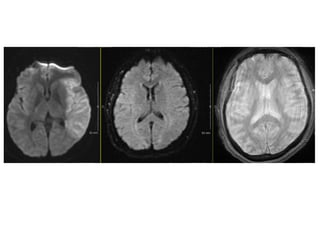

Mme M

• 44 ans

• Antc: rétrécissement mitral secondaire à un

rhumatisme articulaire aigu

• Pas de traitement en cours

• HDM:

– consulte le 22.03.2014 à 22h aux urgences pour

douleur lombaire gauche (suspicion colique

néphrétique)

– 23h30 retrouvée avec une hémiplégie gauche.

• Appel neurologue de garde: NIHSS 14

• ECG: ACFA

• Patiente thrombolysée par voie intraveineuse à

00h10

• Transfert en neuroradiologie à 1h10; score

NIHSS 14

• Thrombéctomie mécanique

• NIHSS en fin de procédure – 3

• Instauration d’une anticoagulation efficace

• Le 25 mars 2014 – aggravation neurologique

avec apparition d’une aphasie et d’une

hémiplégie brachio-faciale droite